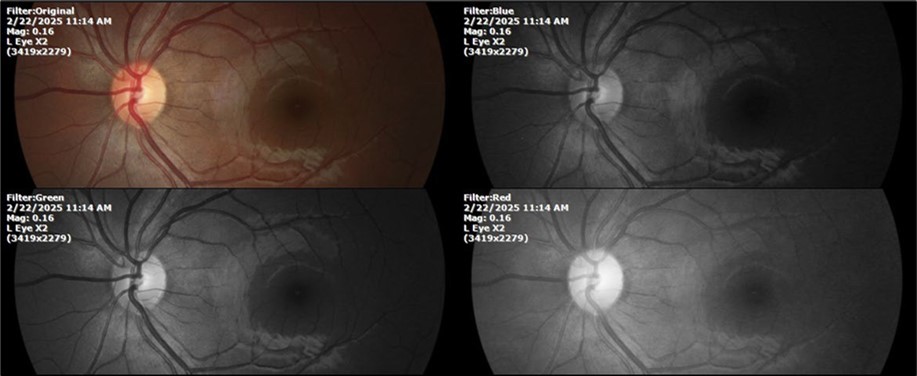

February 22, 2025

There is no pain, only minimal discomfort, and my vision has improved (Figure 20, Figure 21, Figure 22, Figure 23, Figure 24)

SpO2 %: 91 %

Heartbeat: 67 x´

Sciascopy: ++/++

Figure 20.The mirror reflection of the affected (right) eye continues to improve.

The mirror reflection of the affected (right) eye continues to improve.

Figure 21.The anterior segment of the right eye responds with difficulty to mydriatics, which is usual in diseased eyes.

The anterior segment of the right eye responds with difficulty to mydriatics, which is usual in diseased eyes.

Figure 22.The whitish mass of phantom cells continues to decrease. The treatment continues to be based on ǪIAPI 1®, sublingual drops, three drops every hour, for as long as the patient is awake.

The whitish mass of phantom cells continues to decrease. The treatment continues to be based on ǪIAPI 1®, sublingual drops, three drops every hour, for as long as the patient is awake.

Figure 23.The mirror reflection of the left eye, without anomalies.

The mirror reflection of the left eye, without anomalies.

Figure 24.The eye that was not affected by the trauma (left side) remains in good condition.

The eye that was not affected by the trauma (left side) remains in good condition.